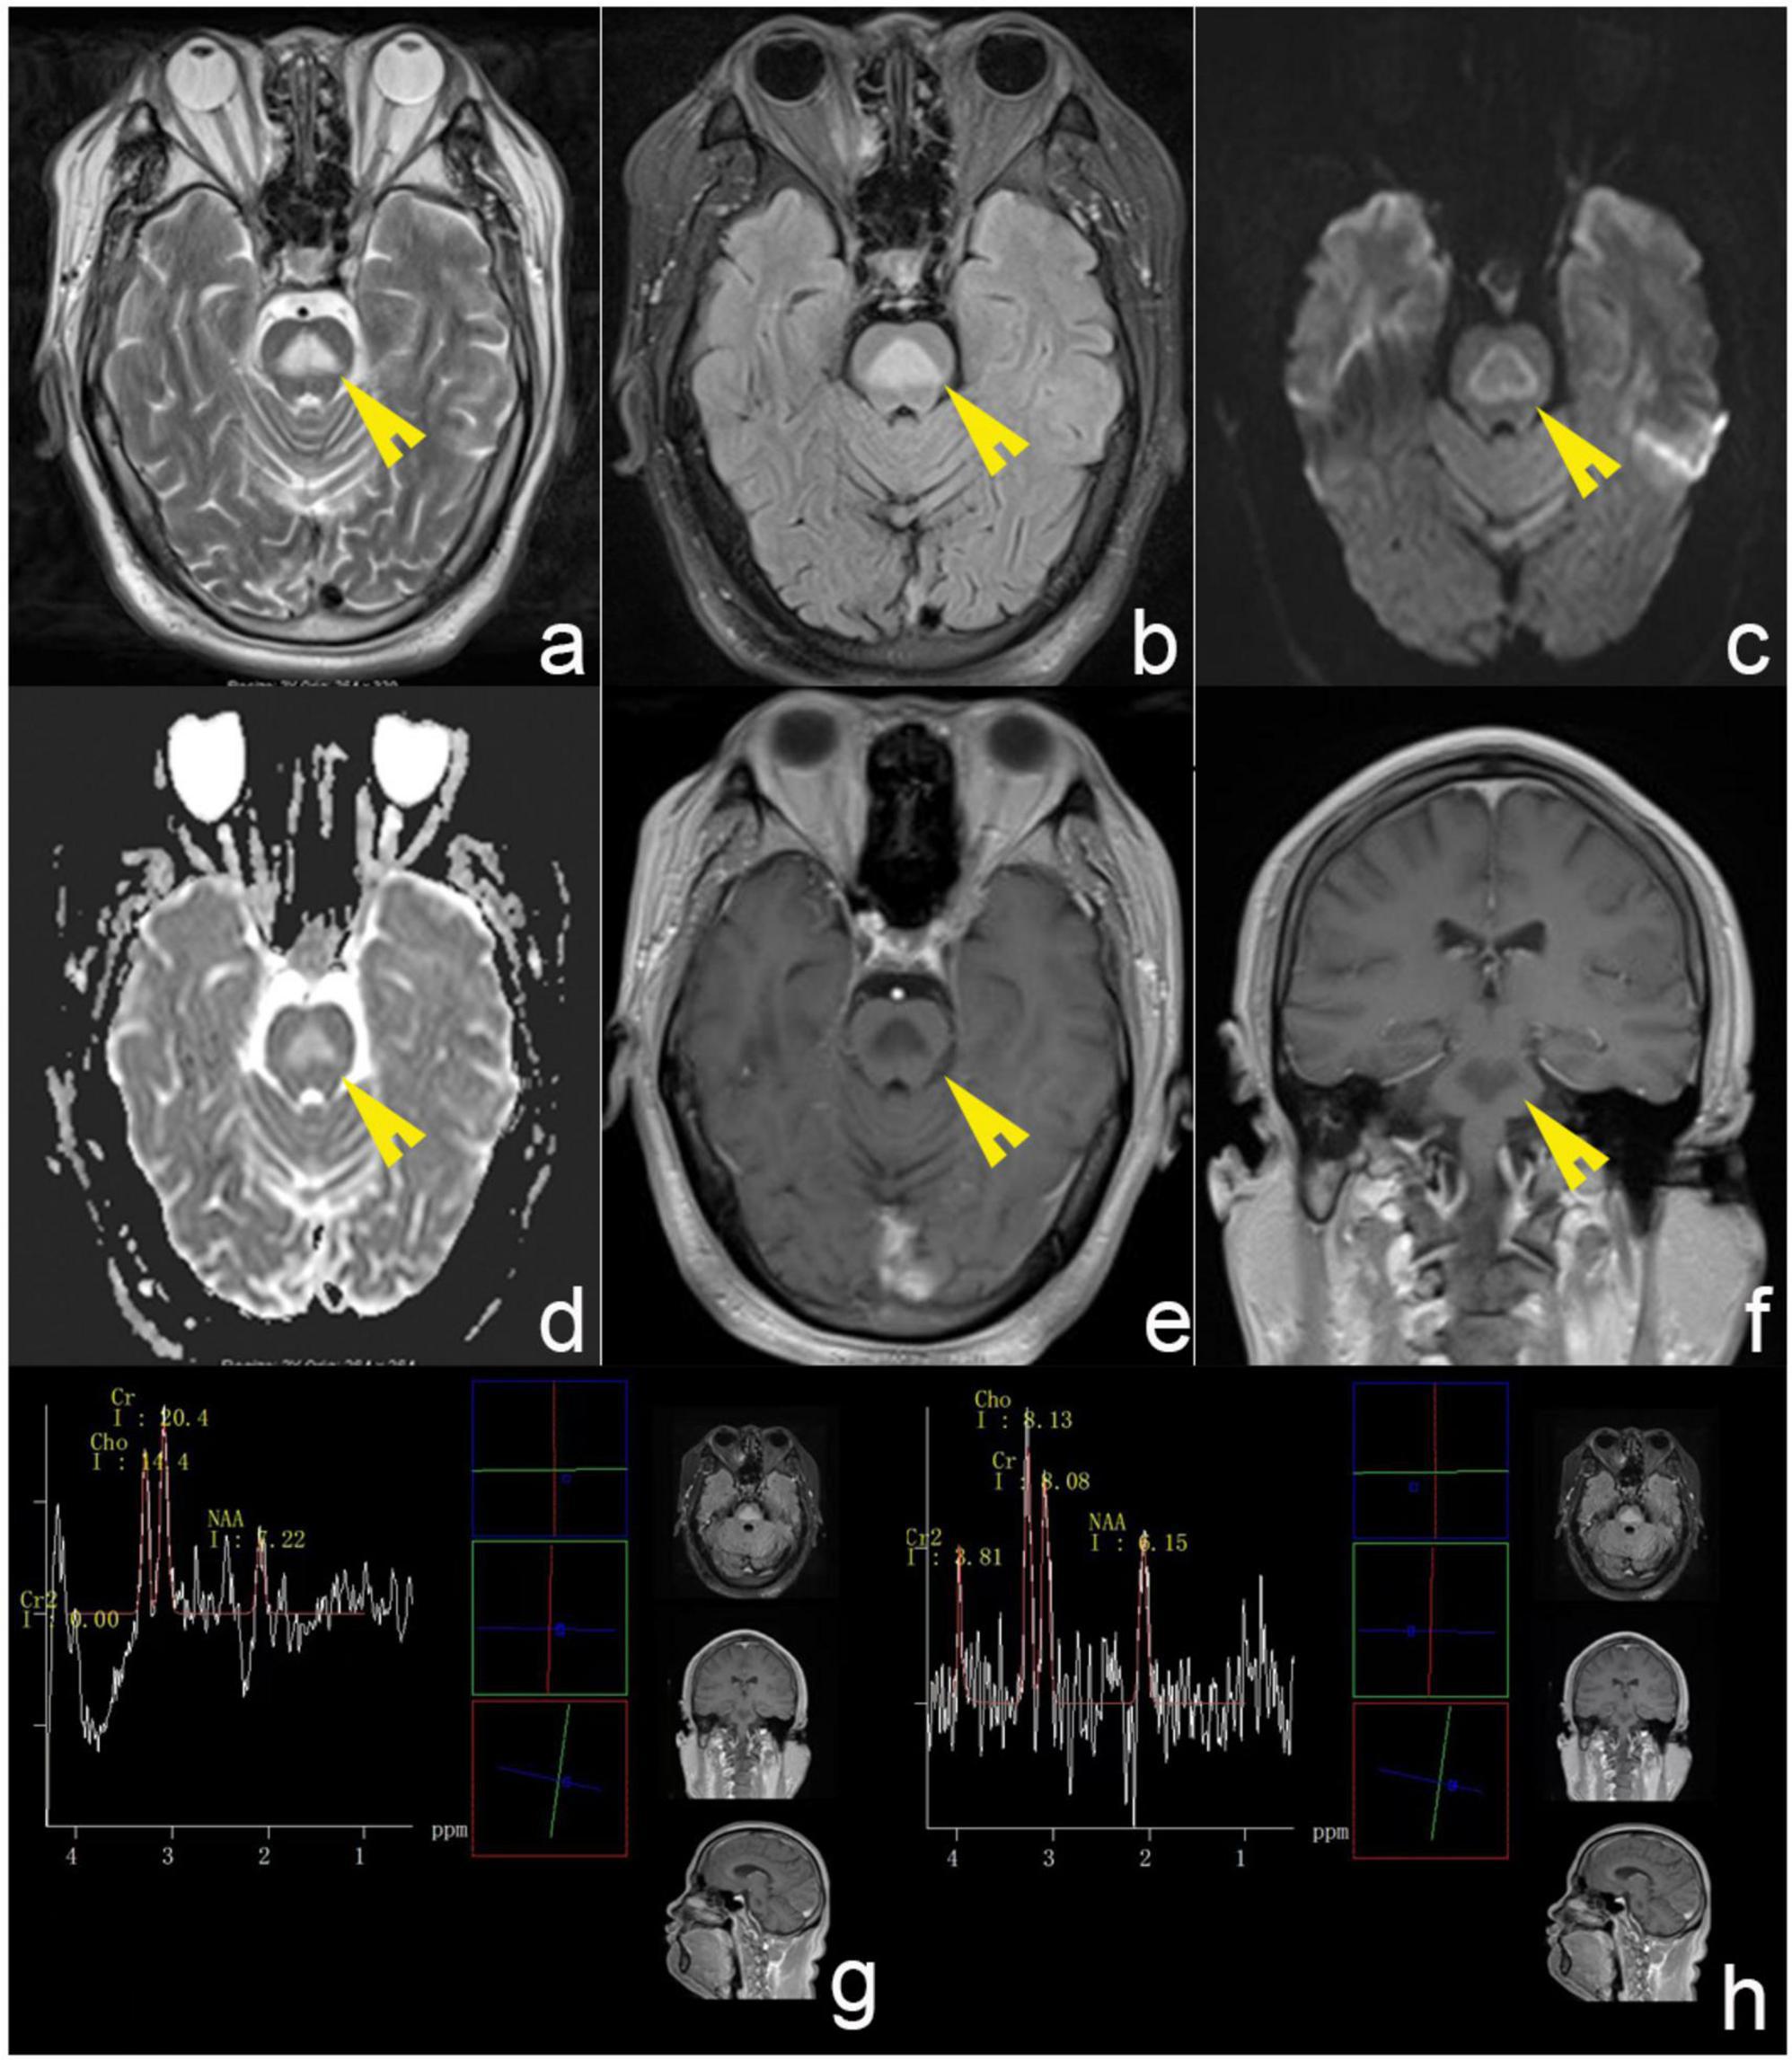

Osmotic demyelination syndrome (ODS), which embraces central pontine myelinolysis and extrapontine myelinolysis, is a well-known but uncommon disorder of the central nervous system. The disease primarily occurs after rapid correction of severe hyponatremia. However, excessive drinking is one of the rare etiologies of ODS. Cases of alcohol-related ODS without documented hyponatremia are rarely reported, and optimal therapeutic approaches remain unclear. We report a patient in his 30's with a history of heavy drinking who presented with unsteady gait and limb tremor as the main clinical manifestations. The patient consistently denied any history of fluid or electrolyte imbalances and reported a normal-range blood sodium level. MRI revealed triangular T2-weighted and FLAIR pontine hyperintensity with a surrounding DWI rim. Finally, the patient recovered completely following corticosteroid treatment. This case shows the possibility that Alcohol-related ODS can occur without electrolyte disturbances and may respond favorably to combined corticosteroid and vitamin B therapy, warranting further investigation in clinical studies. We conducted a literature review of ODS in alcoholic patients and summarized its possible etiology, epidemiology, clinical characteristics and treatment options to raise awareness of such disorders.